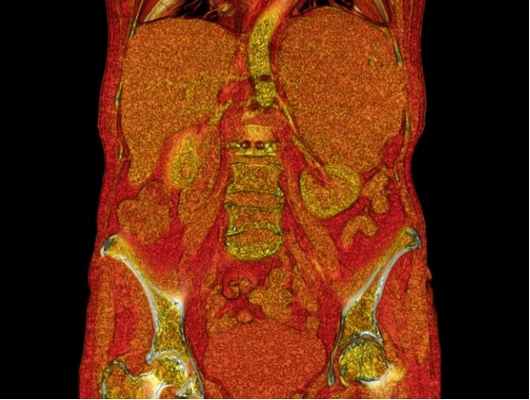

В настоящее время широко используется УЗИ, КТ или МР-томография для выявления расположения опухоли надпочечника, наличия метастазов.

Андростерома гормонально-активная опухоль коры надпочечника, исходящая в основном из ее сетчатой зоны, избыточно выделяющая кортикостероиды, но преимущественно андрогены, и характеризующаяся клинической картиной, сходной с врожденной дисфункцией коры надпочечников . Заболевание может встречаться в любом возрасте у лиц обоего пола. Решающее значение при постановке диагноза андростеромы имеют данные компьютерной томографии надпочечников. Представлен клинический случай, обучающий основам клиники, дифференциальной диагностики и лечения андро-стеромы.

Андростерома - гормонально-активная опухоль коры надпочечника, исходящая в основном из ее сетчатой зоны, избыточно выделяющая кортикостероиды, но преимущественно андрогены, и характеризующаяся клинической картиной, сходной с врожденной дисфункцией коры надпочечников. Заболевание может встречаться в любом возрасте у лиц обоего пола. Решающее значение при постановке диагноза андростеромы имеют данные компьютерной томографии надпочечников. Представлен клинический случай, обучающий основам клиники, дифференциальной диагностики и лечения андро-стеромы.

роме. Иногда появляются отдельные симптомы, характерные для болезни Иценко-Кушинга, что обусловлено гиперпродукцией глюкокортикоидов. С целью визуализации надпочечников используется РКТ, при этом выявляется чаще односторонняя опухоль надпочечника. Данные РКТ имеют решающее значение при постановке диагноза андростеромы. Дифференциальную диагностику следует проводить с двусторонней вирилизирую-щей гиперплазией надпочечников. Для этого проводят пробы с введением АКТГ и дексаметазона. В связи с определенной автономностью опухоли, т. е. независимостью ее функции от регулирующего влияния гипофиза, введение АКТГ и декса-метазона не сопровождается изменением экскреции 17-КС. Рентгенологическое исследование (супраренографию) сочетают с ретроградной или инфузионной пиелографией. Из других заболеваний, сопровождающихся вирилизацией, следует помнить об опухолях яичников, продуцирующих андрогены, адренобластомах. В этих случаях экскреция 17-КС не изменена или умеренно повышена неадекватно степени вирилизации. Методом диагностики служит гинекологический осмотр и рентгенодиагностика (оксипельвиография). Увеличение яичника с одной стороны дает основания подозревать опухоль. Описаны отдельные случаи развития вирильного синдрома на почве

Компьютерная томография — множественные узловатые образования обоих надпочечников. Аденомы. При гистологическом исследовании биоптата — темно-клеточная аденома коры надпочечников с массивными кровоизлияниями. УЗИ матки и придатков — состояние соответствует гипоэстрогении.